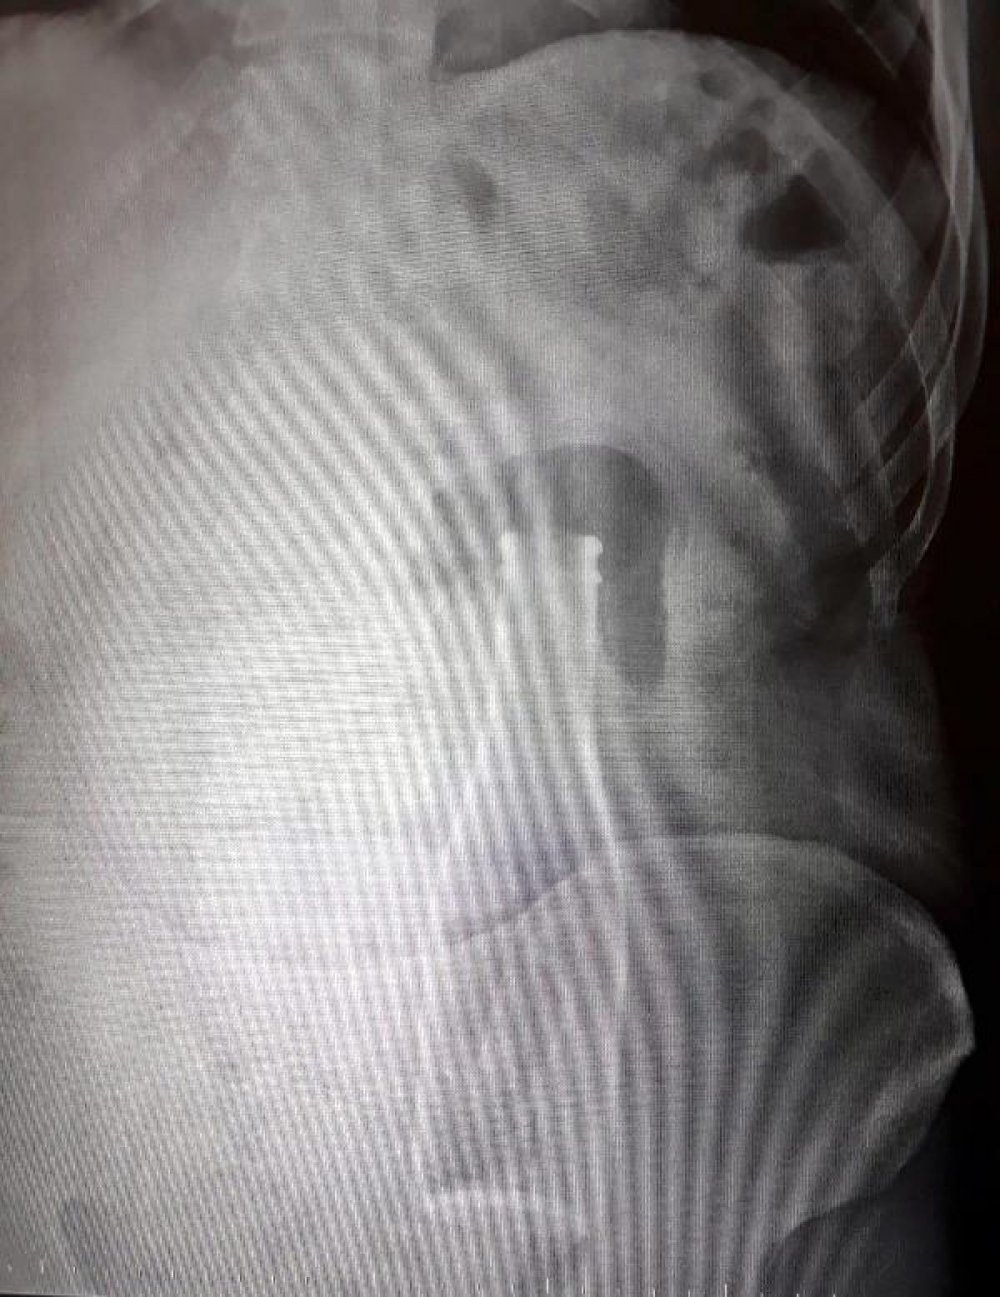

Karaman 'da meydana gelen olayda bir kişi , geçtiğimiz gün karın ağrısı şikayetiyle hastaneye gitti. Karın ağrısı ile hastaneye giden Afganistan uyruklu A.E. adlı erkeğin hastanede tetkikleri yapıldı ve röntgeni çekildi. Çekilen röntgende şaşırtan bir durum ortaya çıktı.

Röntgende görülen görüntü doktorları şaşırttı. Afganistan uyruklu A.E. 'nin karnında kalın bağırsağında bir şişe olduğu ortaya çıktı.